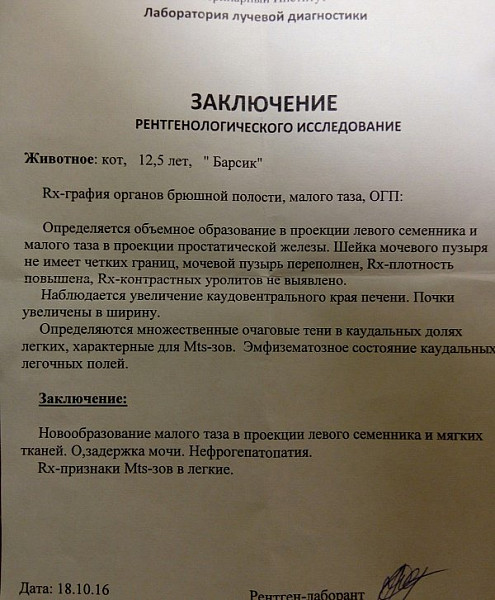

Нормы обзорной рентгенографии брюшной полости